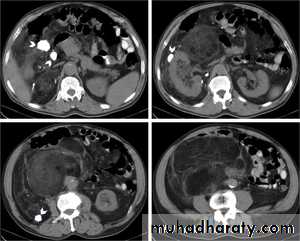

Retroperit abscess